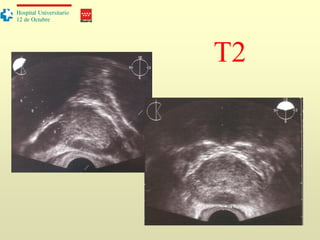

Estadificación

T2: tumor localizado dentro de la próstata

T2